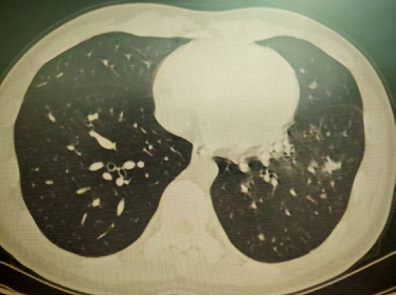

以上是他的胸部CT影像,主要表现为左下肺炎症,片絮影+磨玻璃影。

肺部感染的影像学特征

多发性结节伴快速进展

CT表现为双肺多发实性结节(直径0.5-3cm),结节边缘可见毛刺征及分叶征,特征性表现为短期内体积呈几何级数增长(如1周内增大10倍),需与转移瘤、结核球等鉴别。

混合性密度影与胸腔积液

约40%病例出现磨玻璃影与实变影共存,部分结节中央可见液化坏死;30%伴单侧渗出性胸腔积液,积液分析呈渗出性但培养阴性,此表现易误诊为脓胸。

明确诊断后我们给予了正规治疗,患者咳嗽症状迅速缓解,1月后复查胸部CT提示肺部病变大部分吸收。

4月后再次复查胸部CT,提示病灶已经完全吸收。